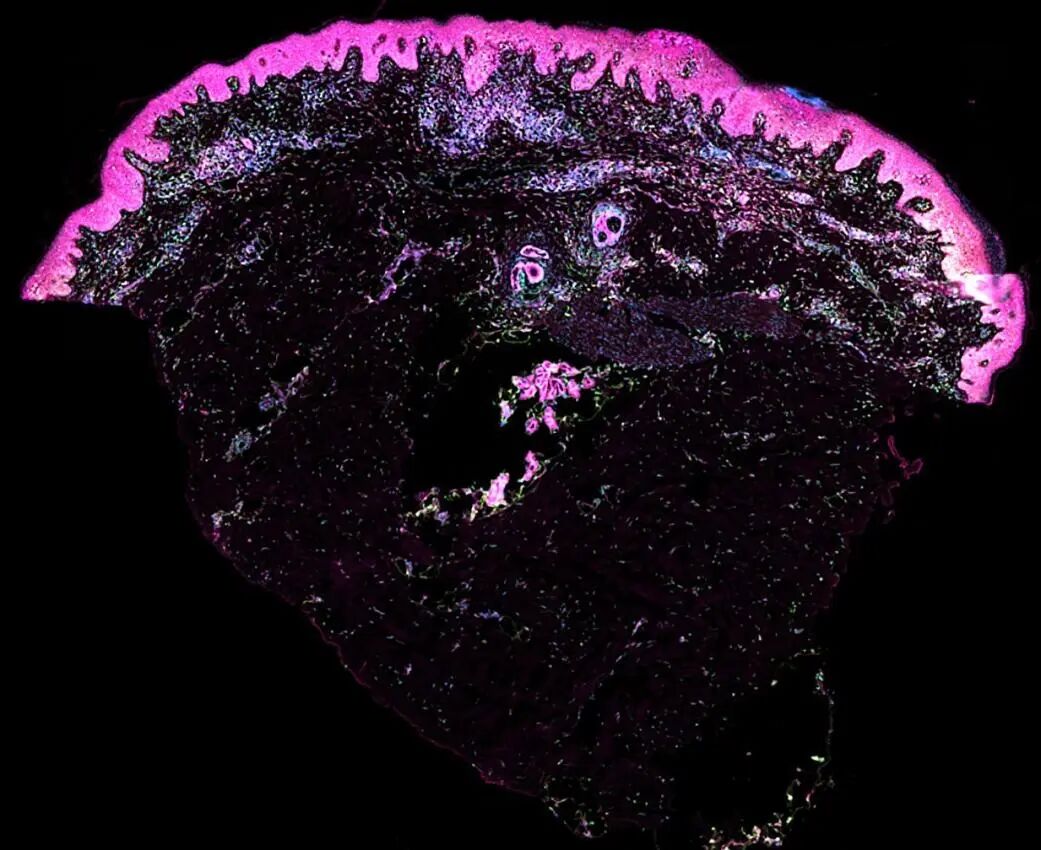

图片

△ 巨噬细胞支持产前皮肤血管生成

△ 人类皮肤细胞(青色:干细胞。橙色:角质细胞。绿色和紫色:免疫细胞),来源:威康桑格研究所